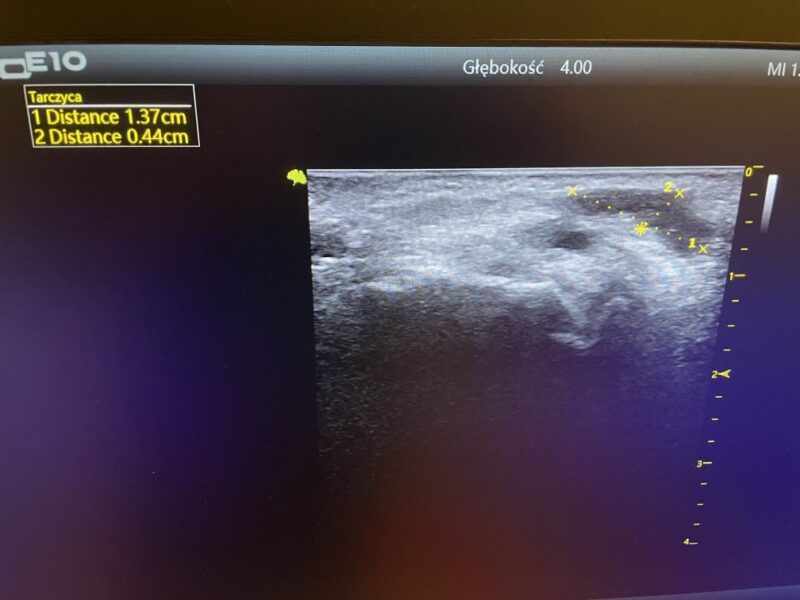

Najskuteczniejsze w tym wypadku będzie wykonanie USG|